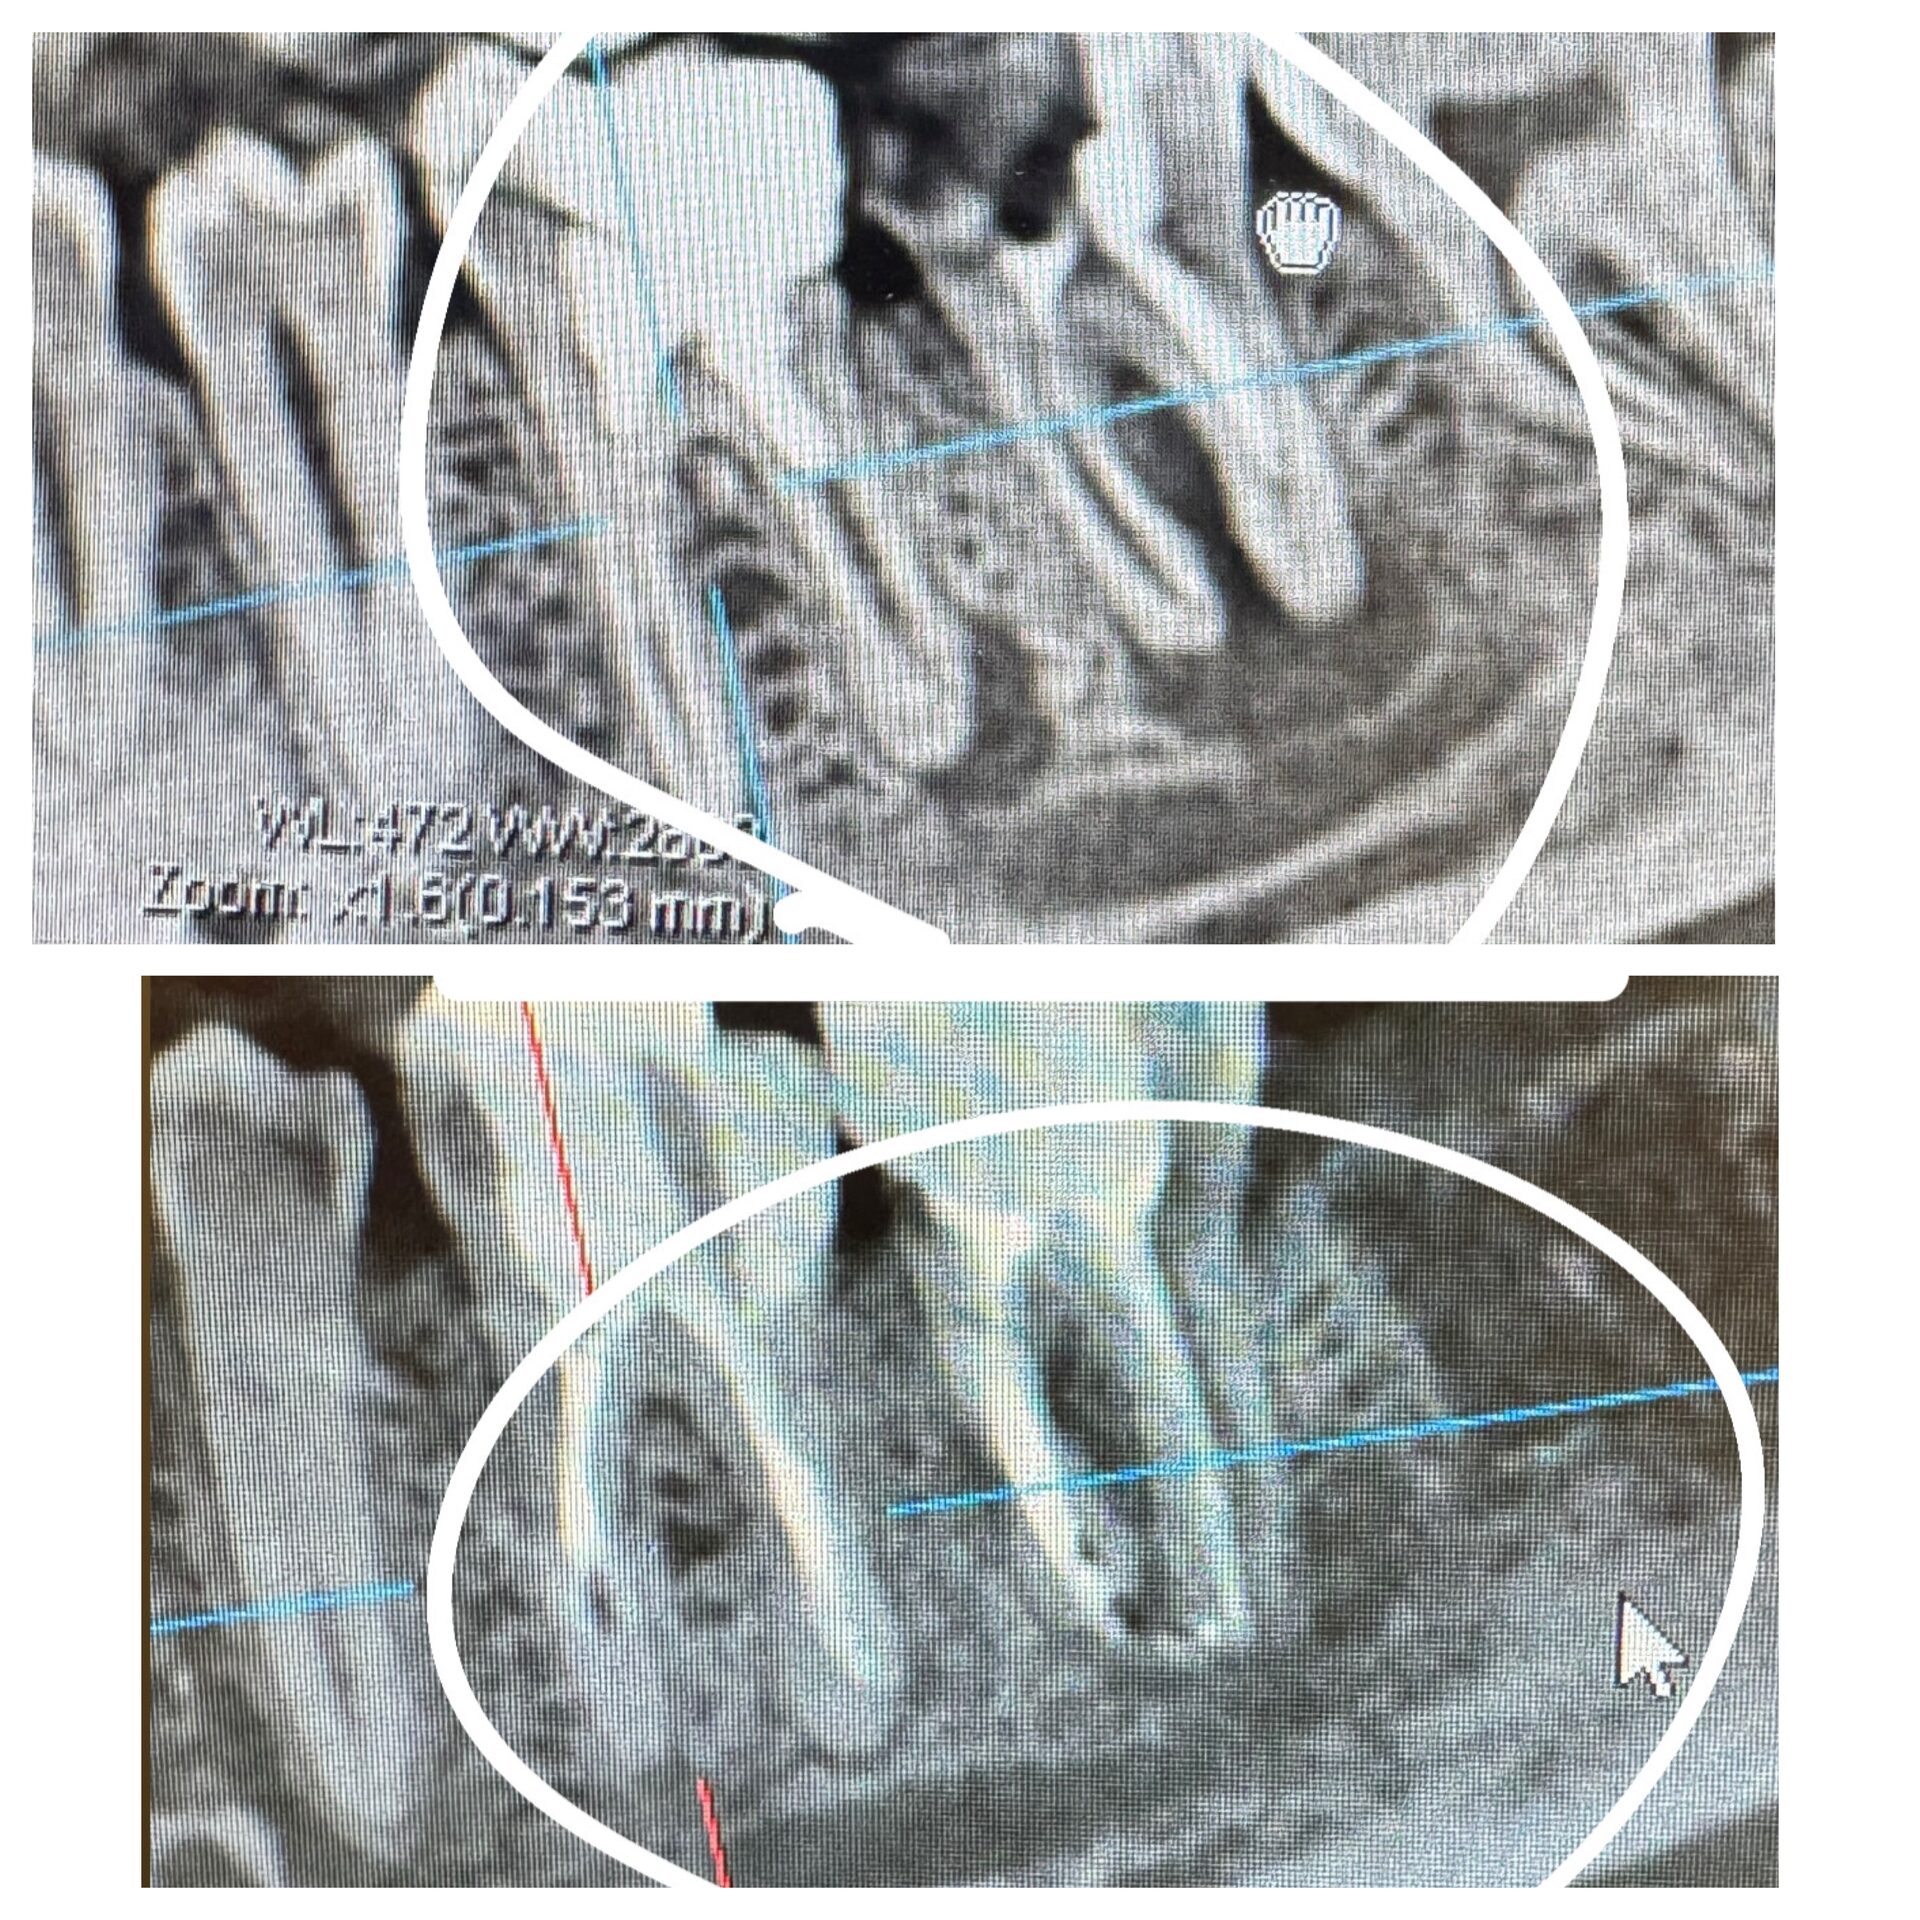

Имплантация зубов с хирургическим шаблоном